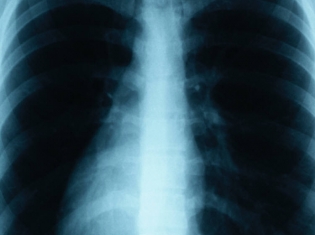

Treating Pulmonary Hypertension

Pulmonary hypertension occurs when tiny blood vessels in the lungs narrow, causing elevated blood pressure in the lungs, and ultimately enlarging the heart's pumping chamber as it struggles to get blood inside the lungs. It is progressive and can be a fatal condition.